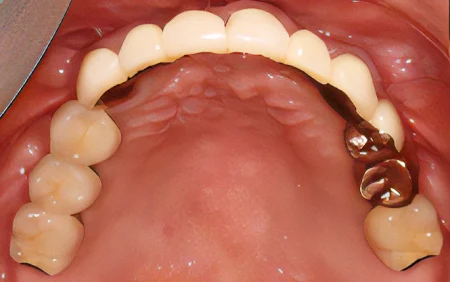

2024.12.1560代男性 痛みのあるブリッジを除去してインプラントブリッジを併用し噛み合わせを改善した症例